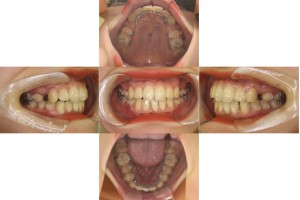

1年経過の口腔内の状態です。

抜歯した箇所のスペースが閉じてきました。